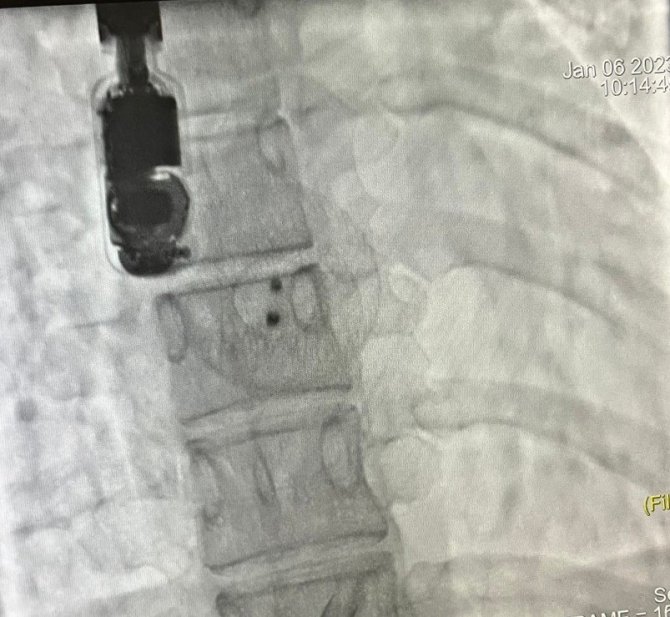

İşlemden bir gün önce Kardiyoloji servisine yatırılan hastanın hazırlıklarının tamamlanmasıyla Femoral (kasık) damarından katater yardımı ile girildi. ASD kapama, anjiografik yöntem kullanılarak tek seansta başarı ile yerleştirildi. Anjiografik yöntem ile genel anestezi olmadan derin sedasyon yöntemi ile yapılan işlem sayesinde hem hastanın yatış süresi kısalırken, cerrahi kesi izi olmadan işlem tamamlandı. İşlem sonrasında Kardiyoloji Servisi'nde takip edilen hasta, şifa ile 2 gün sonrasında taburcu edildi.

Ameliyatsız yöntemin anjiyo benzeri bir prosedürle lokal anestezi ve hafif sedasyon ile gerçekleştirildiğini dile getiren Doç. Dr. Kayapınar, "Hastanın bacak toplardamarından kalbe ulaşılarak şemsiye benzeri bir cihazla defekt kapatılır. İşlem sonrasında hastanede bir gün takip edildikten sonra medikal tedavisi düzenlenerek taburcu edilir. Bu işlemden sonra tekrar bir defekt oluşma ihtimali çok düşüktür, nadiren cihaza bağlı olumsuzluklar yaşanabilmektedir. Diğer bir seçenek ise Anjio ile deliğin kapatılmasının uygun olmadığı durumlarda (çok büyük delik olması, büyük damarların komşuluğunda delik olması, birden fazla delik gibi) genel anestezi altında ve ameliyathane koşullarında ameliyat ile bu deliğin dikilerek ya da yama konularak kapatılmasıdır. Her iki yöntemde Düzce Üniversitesi Hastanesi'nde başarı ile gerçekleştirilmektedir" şeklinde açıklamasını tamamladı.